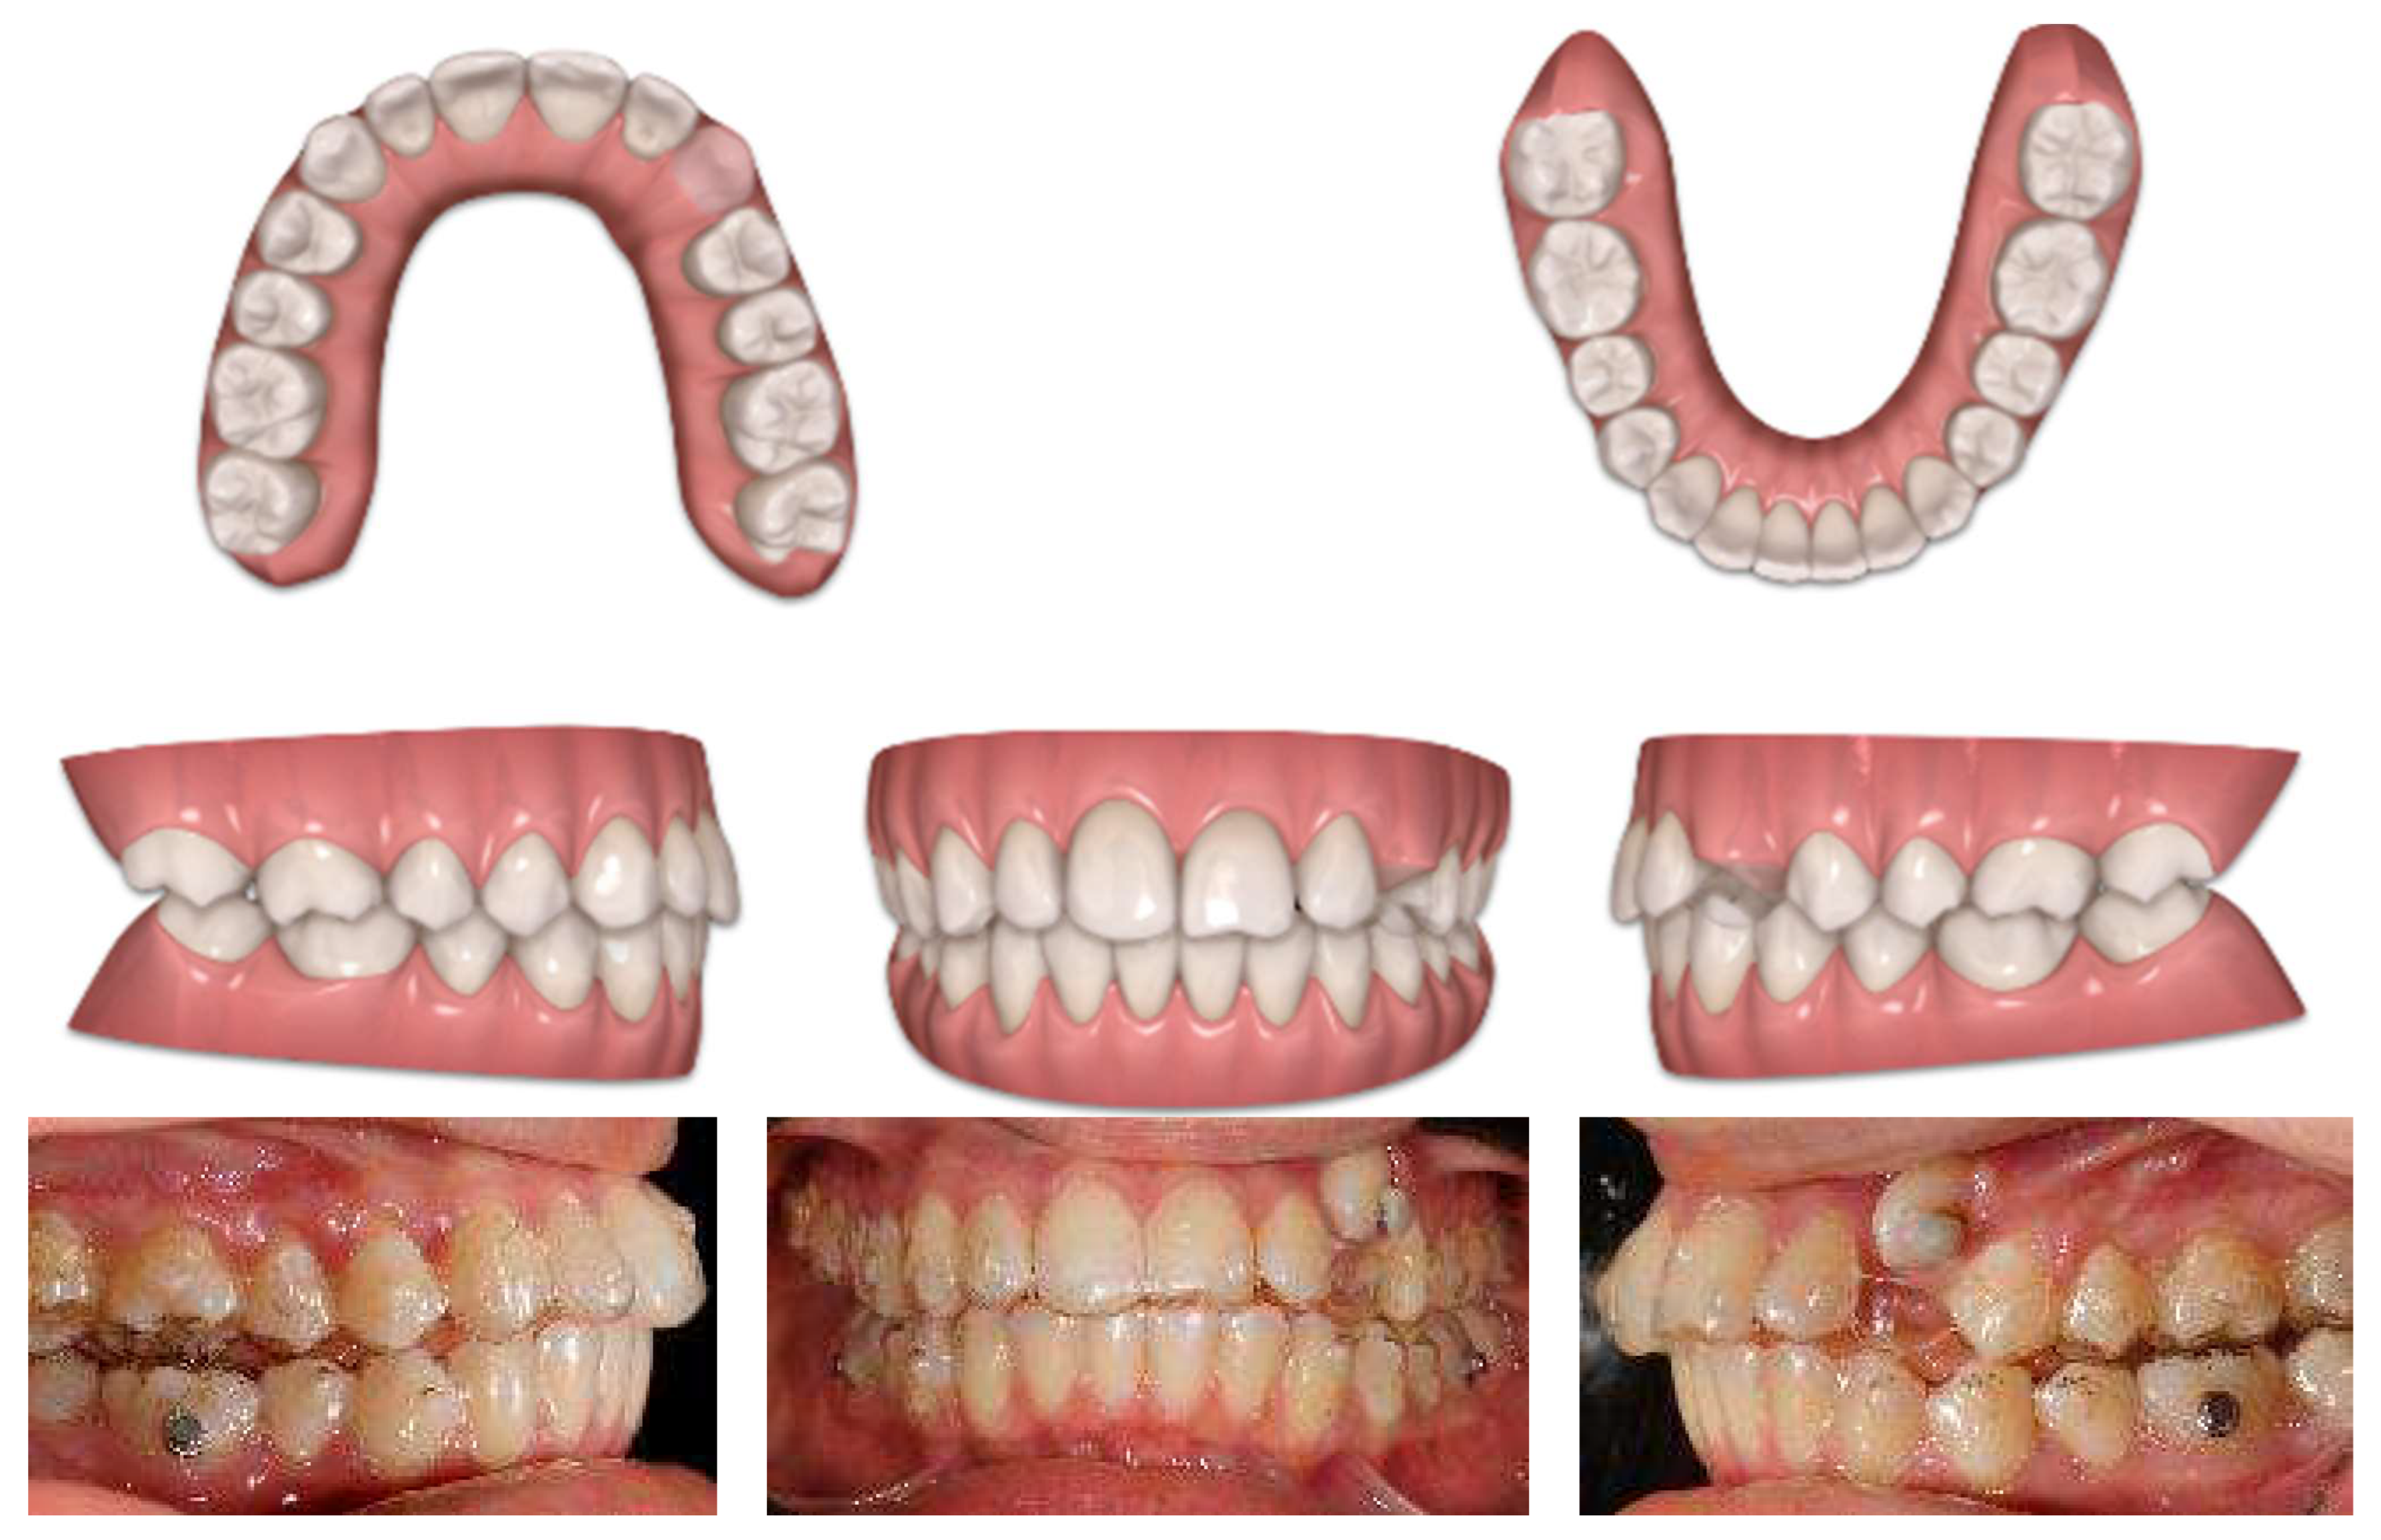

4.2. Results

Post-treatment records of the patient successfully treated using a combination of cantilever mechanics with TADs and clear aligners show a control of the facial aesthetics from the frontal and lateral perspectives with a harmonious soft-tissue profile. Final clinical records show good aesthetics and the functional recovery of the upper canines in the arch. A Class I canine relationship was achieved, and overbite and overjet were normalized. The correction of crowding was carried out (Figure 17).

Figure 17.

Post-treatment extraoral and intraoral pictures.

At the end of the treatment, cephalometric radiographs show the good control of the upper and lower inclination. The radiographic evaluation shows an ideal root parallelism and a preserved periodontal health in the canine region (Figure 18). Retention was achieved through Vivera in the upper arch and via a bonded lingual retainer in the lower arch. No TAD failures were observed.